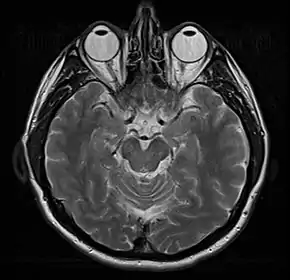

Normal axial T2-weighted MR image of the brain